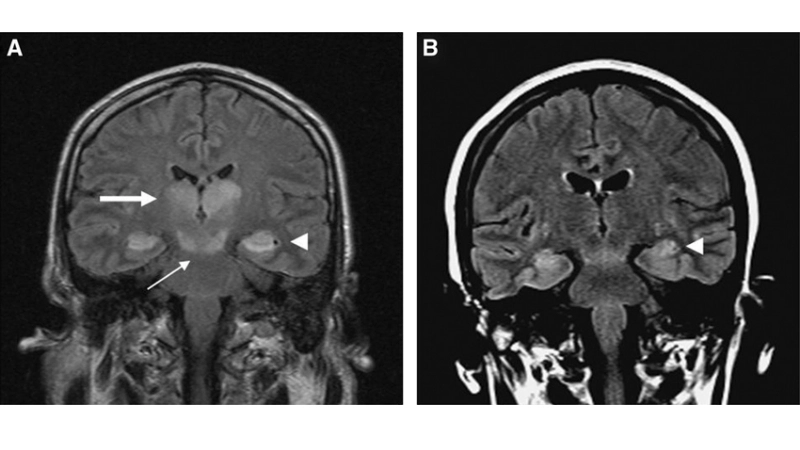

Image description of Murray Valley Encephalitis

Murray Valley Encephalitis is a rare but serious viral infection transmitted by mosquitoes, primarily affecting the brain and nervous system, with potential life-threatening complications.